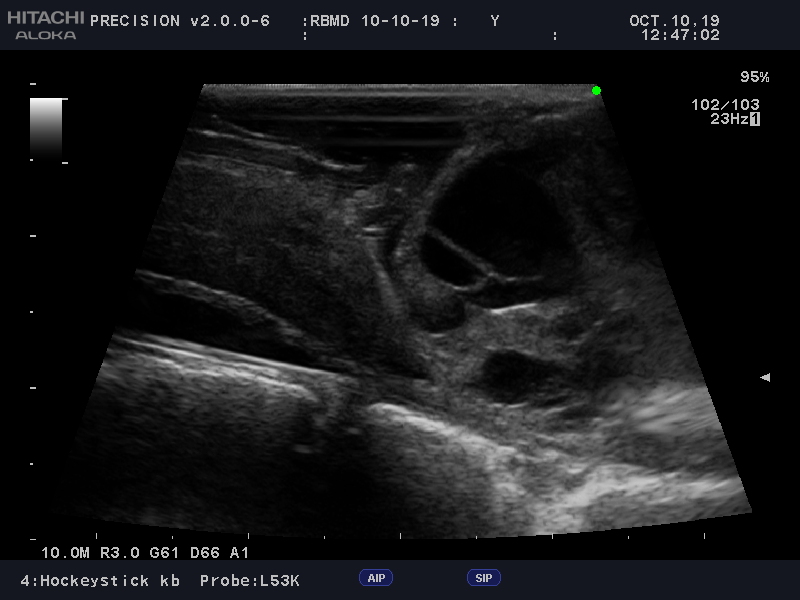

Learn moreArietta Precision

Fujifilm Healthcare’s ARIETTA Precision features state-of-the-art digital architecture and advanced imaging technologies to redefine the capabilities of surgical ultrasound.

Learn moreArietta Precision

Fujifilm Healthcare’s ARIETTA Precision features state-of-the-art digital architecture and advanced imaging technologies to redefine the capabilities of surgical ultrasound.